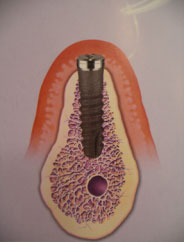

Зубной имплантат - небольшой "искусственный корень", вживляемый взамен утраченного. Имплантат срастается с костью и становится твердой опорой для ваших новых зубов. Если у Вас отсутствует один или несколько зубов, вам не придется обтачивать зубы для установки зубного протеза, если можно установить имплантат, В результате потери зубов на кость уменьшается нагрузка - это приводит к ее атрофии, и смещению зубов в строну дефекта. Со временем появляются морщины вокруг рта, меняется контур лица.

Имплантат будет оказывать нагрузку на кость при жевании, а коронки на имплантате будут поддерживать губы и щеки, помогут вам выглядеть достойно и сохранят форму вашему лицу. Преимушества имплантации 1. Установив имплантат, не придется обтачивать зубы для установки зубного протеза! 2. Имплантат можно установить вместо удаленного зуба в течение одного дня вместе с временной коронкой! 3. Установив имплантат, Ваш съемный протез станет несъемным! 4. Имплантат удержит съемный протез во рту, чтоб протез не выскочил изо рта в самый неподходящий момент. 5. Протезируясь металлокерамическими протезами на имплантате, вкусовые ощущения пищи не изменятся в отличие от съемных протезов которые могут искажать вкус пищи. 6. Установив металлокерамическую коронку на имплантат, улучшается эстетика: уменьшаются морщины вокруг рта, лицо и улыбка молодеет. 7. Установив имплантат улучшается эстетика – коронка на имплантате выглядит так же, как собственный зуб. 8. Установив металлокерамическую коронку на имплантат, Вы восстанавливаете жевательную эффективность на 90%. 9. Уменьшается атрофия альвеолярного гребня кости, восстанавливается нагрузка на кость. 10. После протезирования на имплантате ваше пищеварение будет улучшено, так как пища будет лучше разжевываться и измельчаться, это нормализует работу желудочно-кишечного тракта.